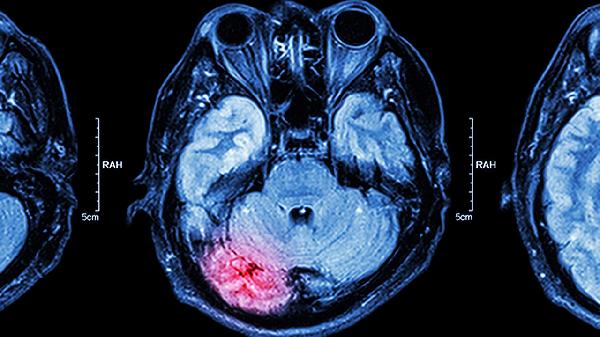

脑脓肿抽吸术有哪些优点

脑脓肿抽吸术具有创伤小、恢复快、定位精准、并发症少、可重复进行等优点。该手术通过影像引导精准定位脓肿位置,利用穿刺针抽取脓液并注入抗生素,能有效降低颅内压并控制感染。 脑脓肿抽吸术采用微创技术,仅需